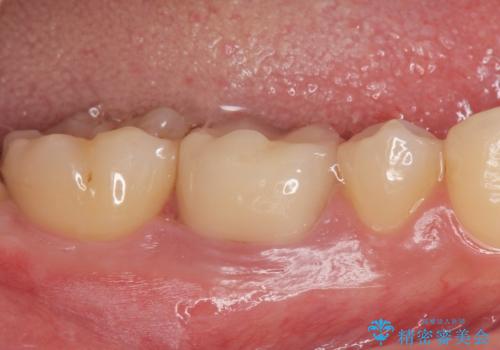

適合の良い被せ物が入りました。